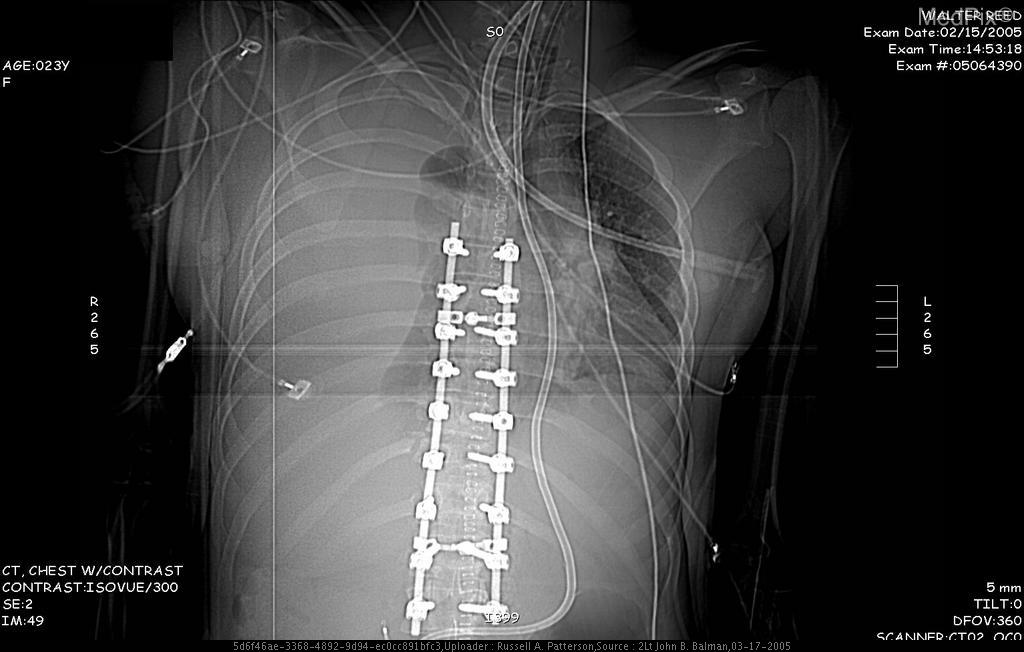

Fusion of your spinal segments can occur naturally if the bones in your spine grow together and the body produces bone tissue that connects them, but more frequently the bones are fused through a surgical procedure to limit the motion at that segment and to decrease any nerve pinching and pain that is happening. The nerve pinching could be caused by a disc injury or loss of disc height, arthritis, or bone spurs at the joints. Fusion is most commonly done in the neck or low back and it is done to improve the stability at that segment. It is very important to learn how to use your muscles surrounding the area of fusion to further stabilize the spine and to limit any other damage to the segments above and below the area of surgery. At Goodell PT we can teach you safety techniques, strengthening, biomechanics, and help to decrease your pain with manual therapy and scar mobilization.